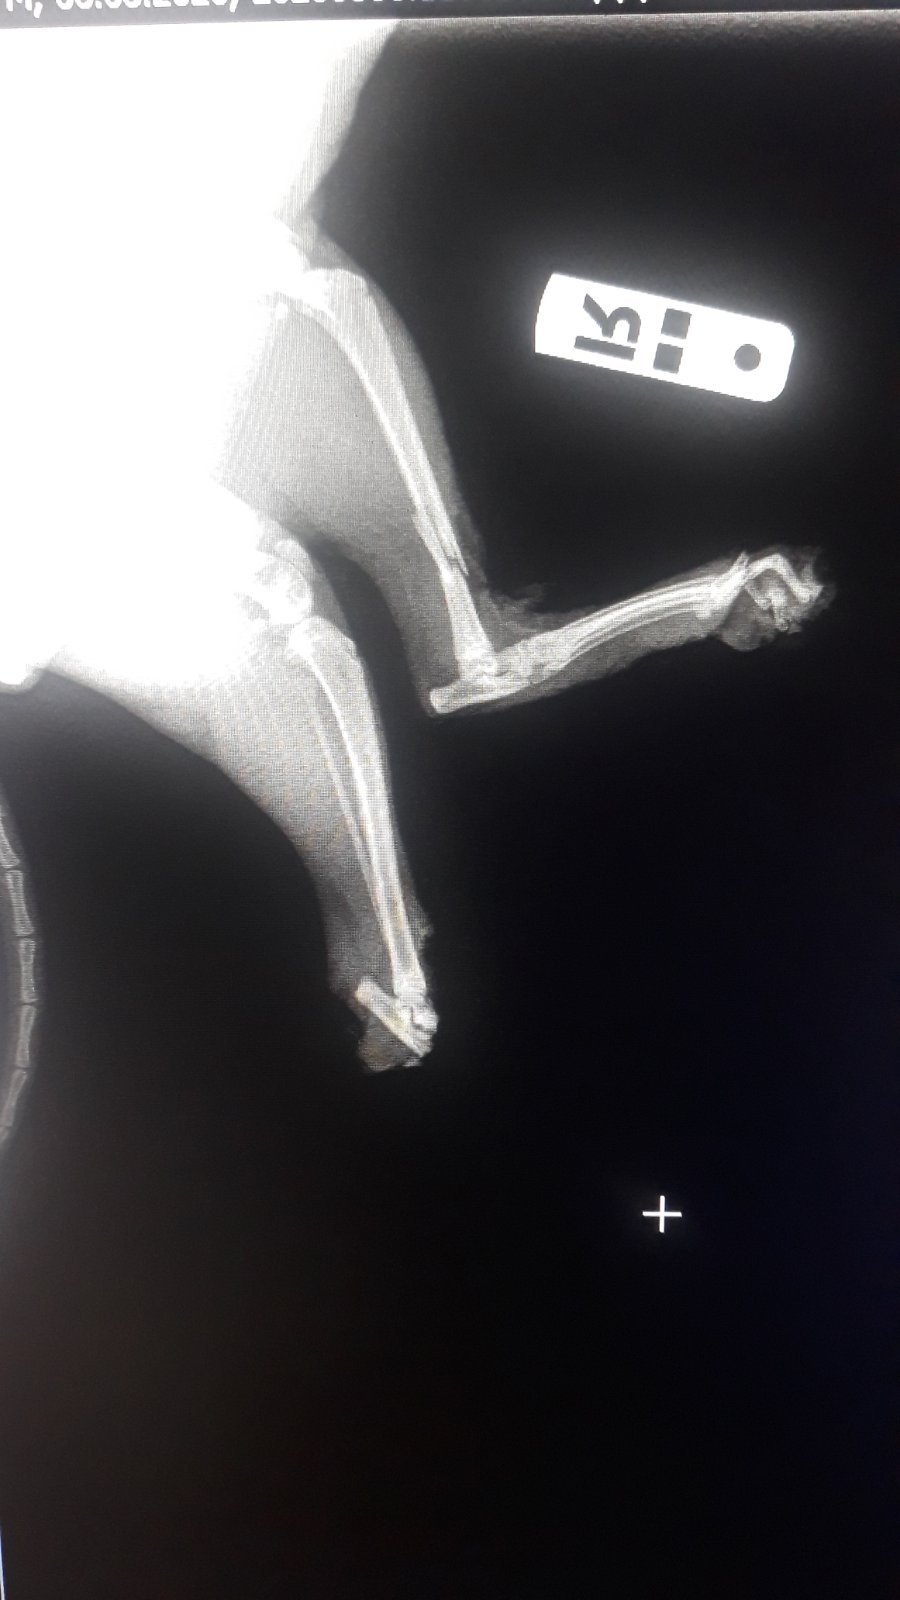

В состоянии шока кошечка попала сразу на операционный стол. Времени на ожидание сбора не было. "Тяжелый оскольчатый перелом задней лапки, оторваны несколько пальчиков. Вторая лапка задняя по колено оторвана (провели ампутацию культи). Передняя лапка разрублена. Между пальчиками глубокие раны. Из-за черепно-мозговой травмы наркоз Муся перенесла тяжело. Операция была тяжелой", - написала Ольга.